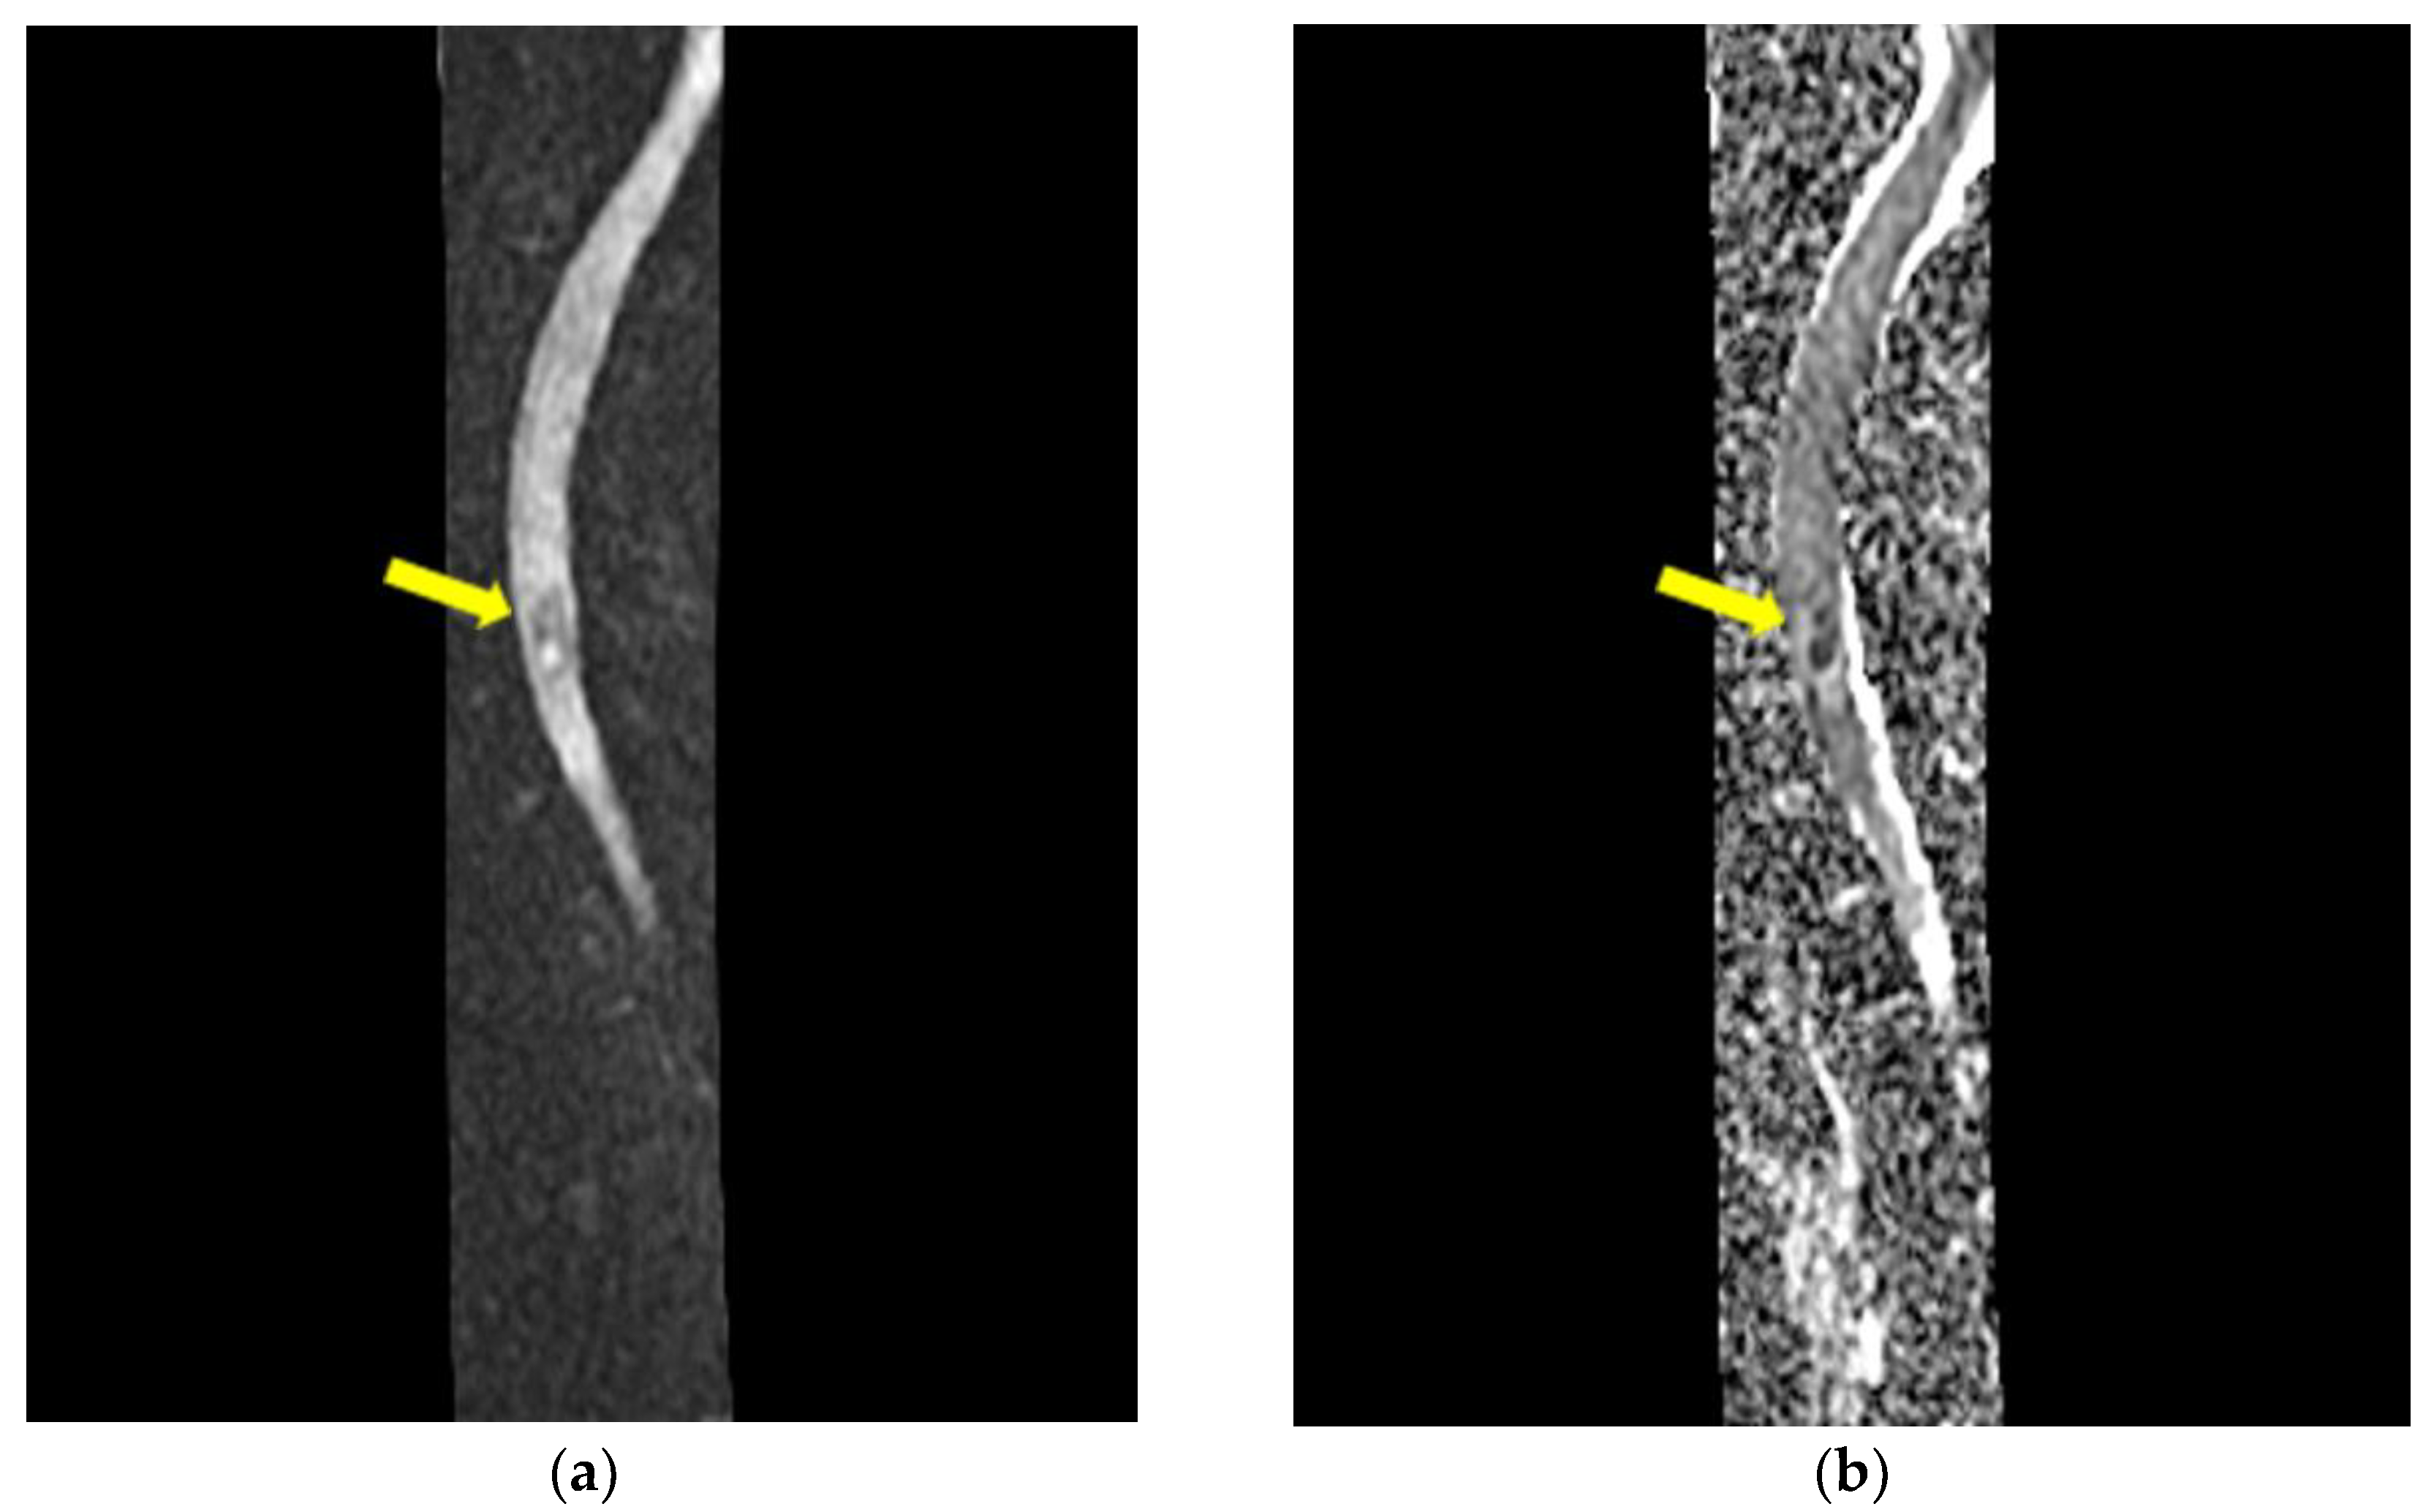

Cervico-Dorsal Intramedullary Spinal Cord Abscess with Aspergillus fumigates following Pulmonary Infection in an Immunocompetent Patient

- Radiological evidence of chronic pulmonary lesion;

- Mycological demonstration of Aspergillus fumigates hyphae by microscopy from spu-tum, microscopy and culture from bronchial aspirate, and histopathological evi-dence of the presence of Aspergillus fumigates hyphae with dichotomous branching in the spinal cord biopsy;